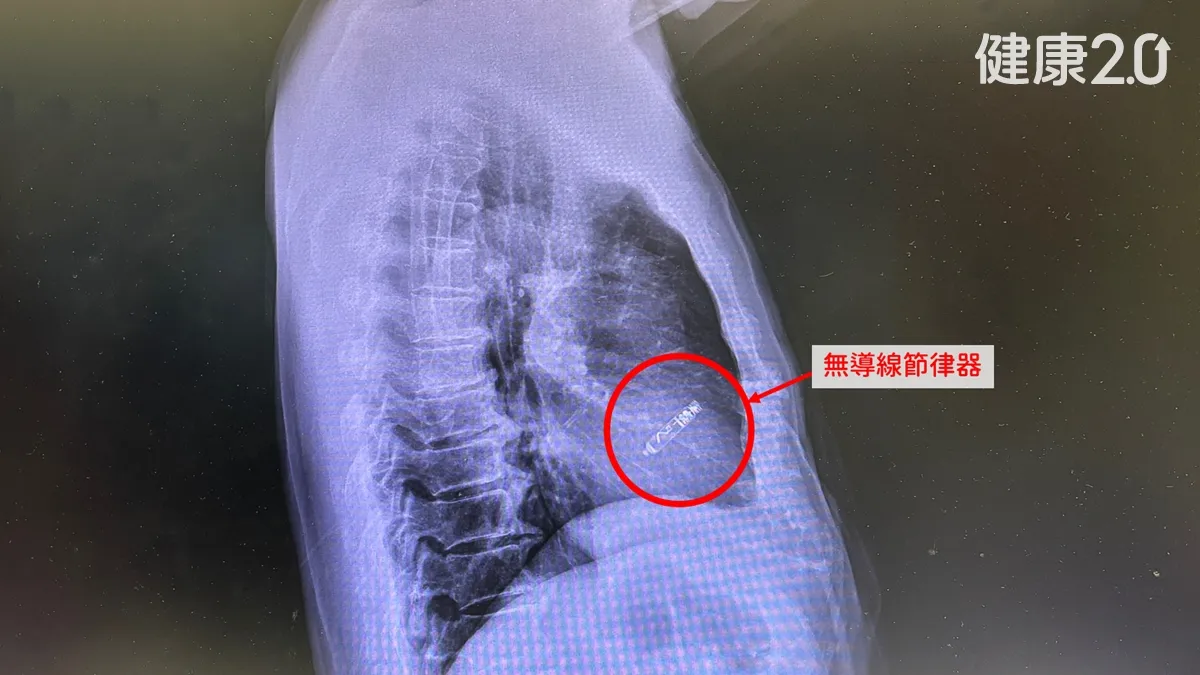

中醫大新竹附醫醫療團隊為這名患者裝的無線節律器,最大好處是沒有導線,所以胸前不會有傷口,節律器透過導管從鼠蹊部股靜脈送入心臟,固定在心臟的右心房或右心室內,節律器會釋放電流刺激心房或心室的肌肉收縮,就能改善心跳緩慢的問題,節律器放入的傷口在鼠蹊部,距離心臟很遠,就算發生傷口感染,也不用移除節律器,可大幅降低感染併發症風險,手術時間只需1小時,傷口只有血管穿刺大小,術前住院1晚,術後隔天就可出院。

◎ 圖片來源/中國醫藥大學新竹附設醫院提供